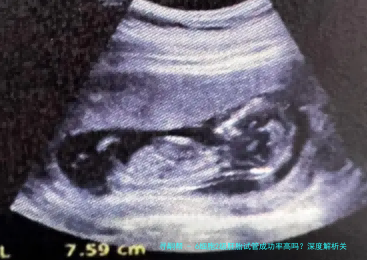

在试管婴儿治疗中,胚胎质量是决计成功率的核心因素。6细胞二级胚胎作为临床多见的中级质量胚胎,实际上际妊娠潜力备受留意。本文将从国际胚胎评介体系体例切入,结合最新临床数据,系统剖析该等级胚胎的着床规则及影响要点。